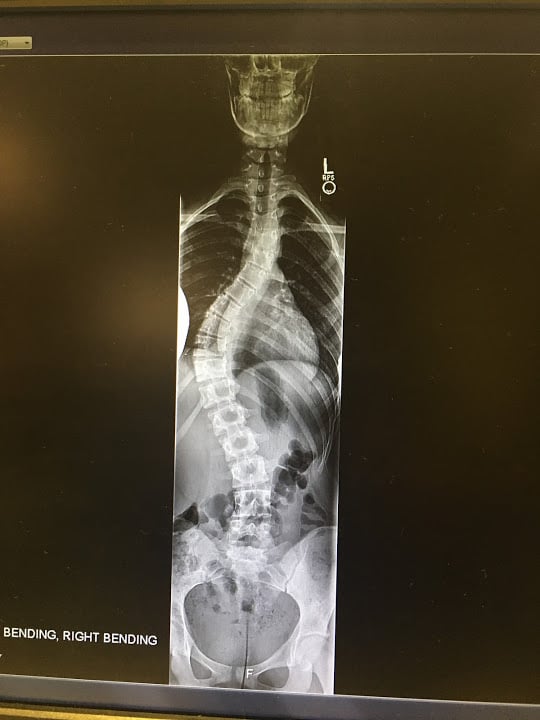

I had an amazing experience at HSS. I was 14 when I had to get a spinal fusion due to an excessive scoliosis curve of over 60 degrees. Dr. Lebl and the staff did an amazing job making sure I was comfortable during my surgery. If I went back in time I would not change a thing I loved my experience at HSS. They had me feeling like myself again within a few weeks, and I was back on the lacrosse field just after 3 months!